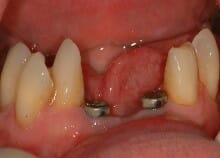

Implant bridges are a great way of replacing a few missing teeth. What some people don’t realise is that we only

need to use 2 implants to replace 4 teeth in the front of the lower jaw.

In this case the gentleman had some very wobbly teeth which he hated to look at at the front of the lower jaw. He

said they were so loose that he had taken to eating only very soft foods.

His fear was that he would have to have a denture – and he hated that idea! His own dentist had offered him one.

We first treated the gum disease to ensure that none of the other teeth in the mouth would suffer the same fate.

Then we removed the 4 wobbly ones and put 2 implants and a temporary bridge in: all on the same day!

The final porcelain bridge was finished within 12 weeks and our gentleman can now eat anything he wants and has

no worries about his teeth falling out during social functions!